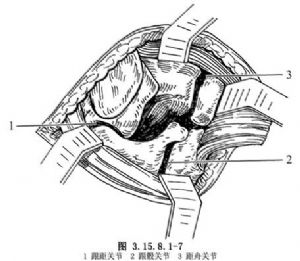

切开皮肤、筋膜组织,不要做皮下浅层分离,防止皮肤坏死。沿切口方向切开踝前十字韧带(图3.15.8.1-4),切口下方的腓骨长短肌腱向下牵拉,将伸趾短肌自跟骨前外侧起点剥离,向远侧翻转,显露跗骨窦,其内有脂肪组织是距跟关节标志(图3.15.8.1-5),清除后切断跟距间韧带,显露距(下)跟关节(图3.15.8.1-6)。在切口上方向前拉开伸趾长肌,在跟骨前即跟骰关节,距骨远端即距舟关节,切开关节囊,足内翻、内收,三个关节都能清楚显露(图3.15.8.1-7)。